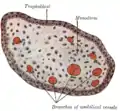

Section through the embryo. Transverse section of a chorionic villus.

Transverse section of a chorionic villus. Human embryo of about 28 days, with yolk-sac.